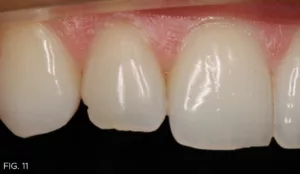

(Note: in smile design, it is ideal that the two centrals be identical. On the other hand, it is normal and visually pleasing for the two laterals to be slightly different.) That said, the defect on #7 was now visually displeasing to the patient and he agreed to a slight shape modification using composite to better match #10. (FIG. 11)

No preparation was made; however, the biofilm was removed with a blaster (Bioclear). Tooth #12 was then etched and a single coat of adhesive (MPa Max, Clinician’s Choice) was applied. The tooth was restored employing a combination of nano-enhanced universal restorative composite (Universal, Evanesce, Clinician’s Choice), white opaquer and grey tint (Creative Color, Cosmedent), and a thin layer of Evanesce Enamel Clear (Clinician’s Choice). After light curing, the restoration was shaped and polished with a medium disc (Sof-Lex, 3M) and polishers (A.S.A.P., Clinician’s Choice). (FIG. 12)

Post-operative close-up retracted right lateral view (1:1) of #5-#9, showing corrected defect on #7 with the use of composite resin.